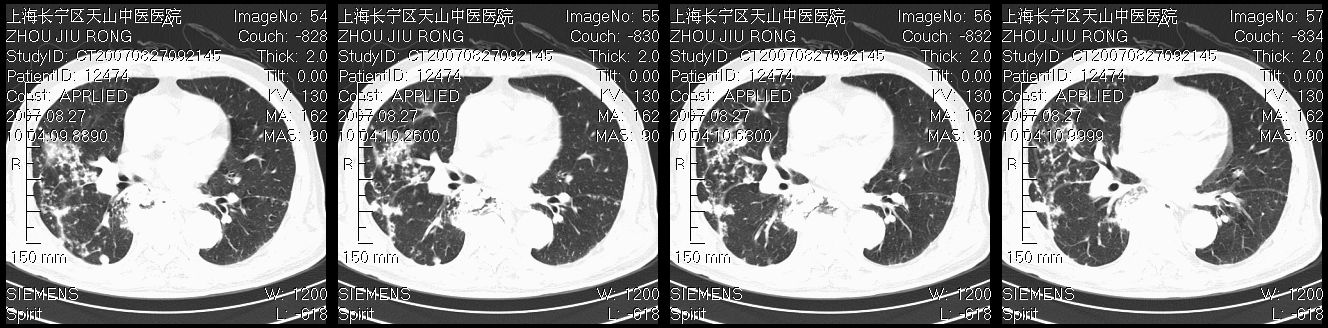

以下是引用zjzjr在2007-8-30 21:47:00的发言:[br]双肺弥漫性结节状、斑片状影,部分形成空洞,病灶以双肺上叶为著(符合结核发病部位),纵隔内见肿大淋巴结影。支持双肺继发性结核伴右上肺空洞形成。

以下是引用zjzjr在2007-8-30 21:47:00的发言:[br]双肺弥漫性结节状、斑片状影,部分形成空洞,病灶以双肺上叶为著(符合结核发病部位),纵隔内见肿大淋巴结影。支持双肺继发性结核伴右上肺空洞形成。

以下是引用gaoshengjiang在2007-8-31 10:24:00的发言:[br]双肺弥漫性斑片状影及多发空洞影,其间夹杂多量条索状影,胸膜肥厚、粘连并有结节状改变,纵隔多枚淋巴结肿大,考虑1双肺继发型肺结核合并感染?2韦格氏肉芽肿?[br] 支持!

以下是引用zjzjr在2007-8-30 21:47:00的发言:[br]双肺弥漫性结节状、斑片状影,部分形成空洞,病灶以双肺上叶为著(符合结核发病部位),纵隔内见肿大淋巴结影。支持双肺继发性结核伴右上肺空洞形成。

以下是引用zjzjr在2007-8-30 21:47:00的发言:[br]双肺弥漫性结节状、斑片状影,部分形成空洞,病灶以双肺上叶为著(符合结核发病部位),纵隔内见肿大淋巴结影。支持双肺继发性结核伴右上肺空洞形成。

以下是引用zjzjr在2007-8-30 21:47:00的发言:[br]双肺弥漫性结节状、斑片状影,部分形成空洞,病灶以双肺上叶为著(符合结核发病部位),纵隔内见肿大淋巴结影。支持双肺继发性结核伴右上肺空洞形成。